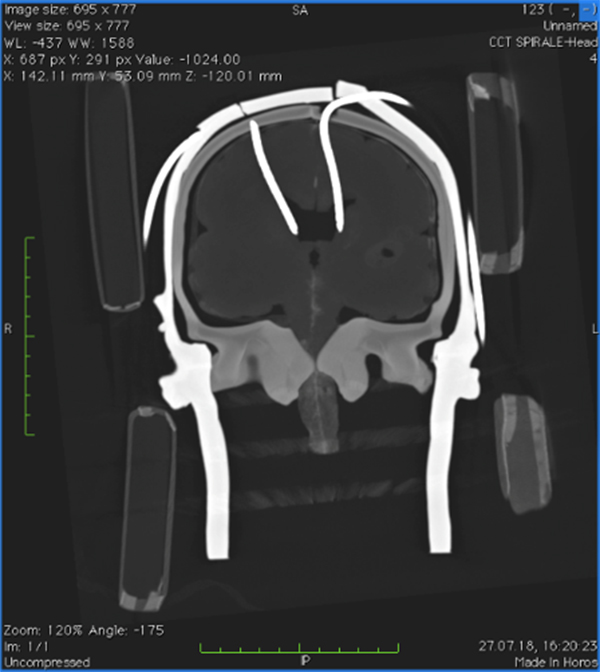

At the Institute of Anthropomatics and Robotics (IAR) of KIT, a system has been developed to process information from CT images in such way that it can be projected onto the head of the operated person using data glasses. The information in the field of view thus supports the surgeons in determining the puncture site and angle. For this purpose, existing CT images are converted into 3D models by conventional image processing. The individual model is computed in just a few seconds. By overlaying the individual patient model with the statistical average, the ideal positioning of the Kocher points in relation to the trepanation on the one hand and the relevant injection points on the other can be visualized. Using data glasses, these points are displayed three-dimensionally on the skull and provide orientation in the surgeon's field of view.